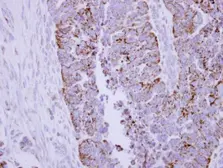

Product

Images

Description

Applications

Reactivity